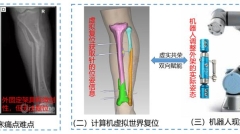

机器人辅助外固定架精准复位系统成果简介

发布:中医药创新转化研究院